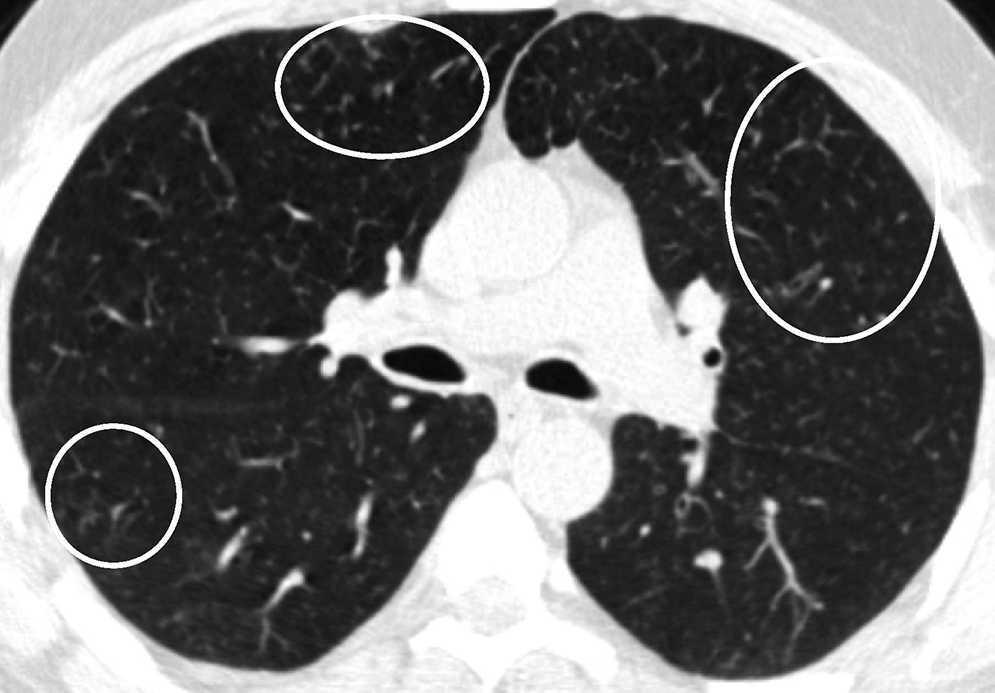

Centrilobular ground-glass nodules were found to be more prominent in the upper lobes of the lungs in thorax computed tomography (CT) (Figure 1a). Abdominal CT and ultrasonography were found to be normal. Endoscopic biopsy for stomach pain was reported as eosinophilic gastritis. Eosinophilic infiltration was observed on transbronchial lung biopsy. Numerous eosinophilic granulocytes (40%) were observed in bone marrow biopsy without increased blast cells. A prominent mast cell population was not observed. There was no malignant infiltration. FIPLI-PDGFRα mutation, JAK-2 mutation and Philadelphia chromosome were also found to be negative.

Figure 1a. Axial CT image at lung window setting showing centrilobular ground-glass nodules (circles).